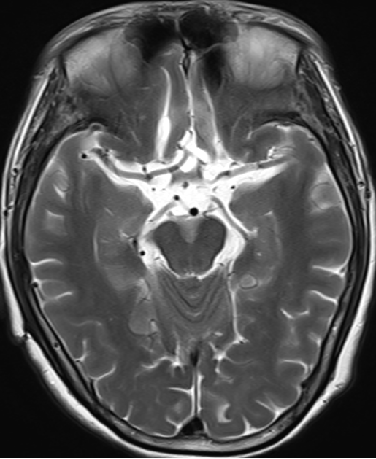

2013-5-16 MRI